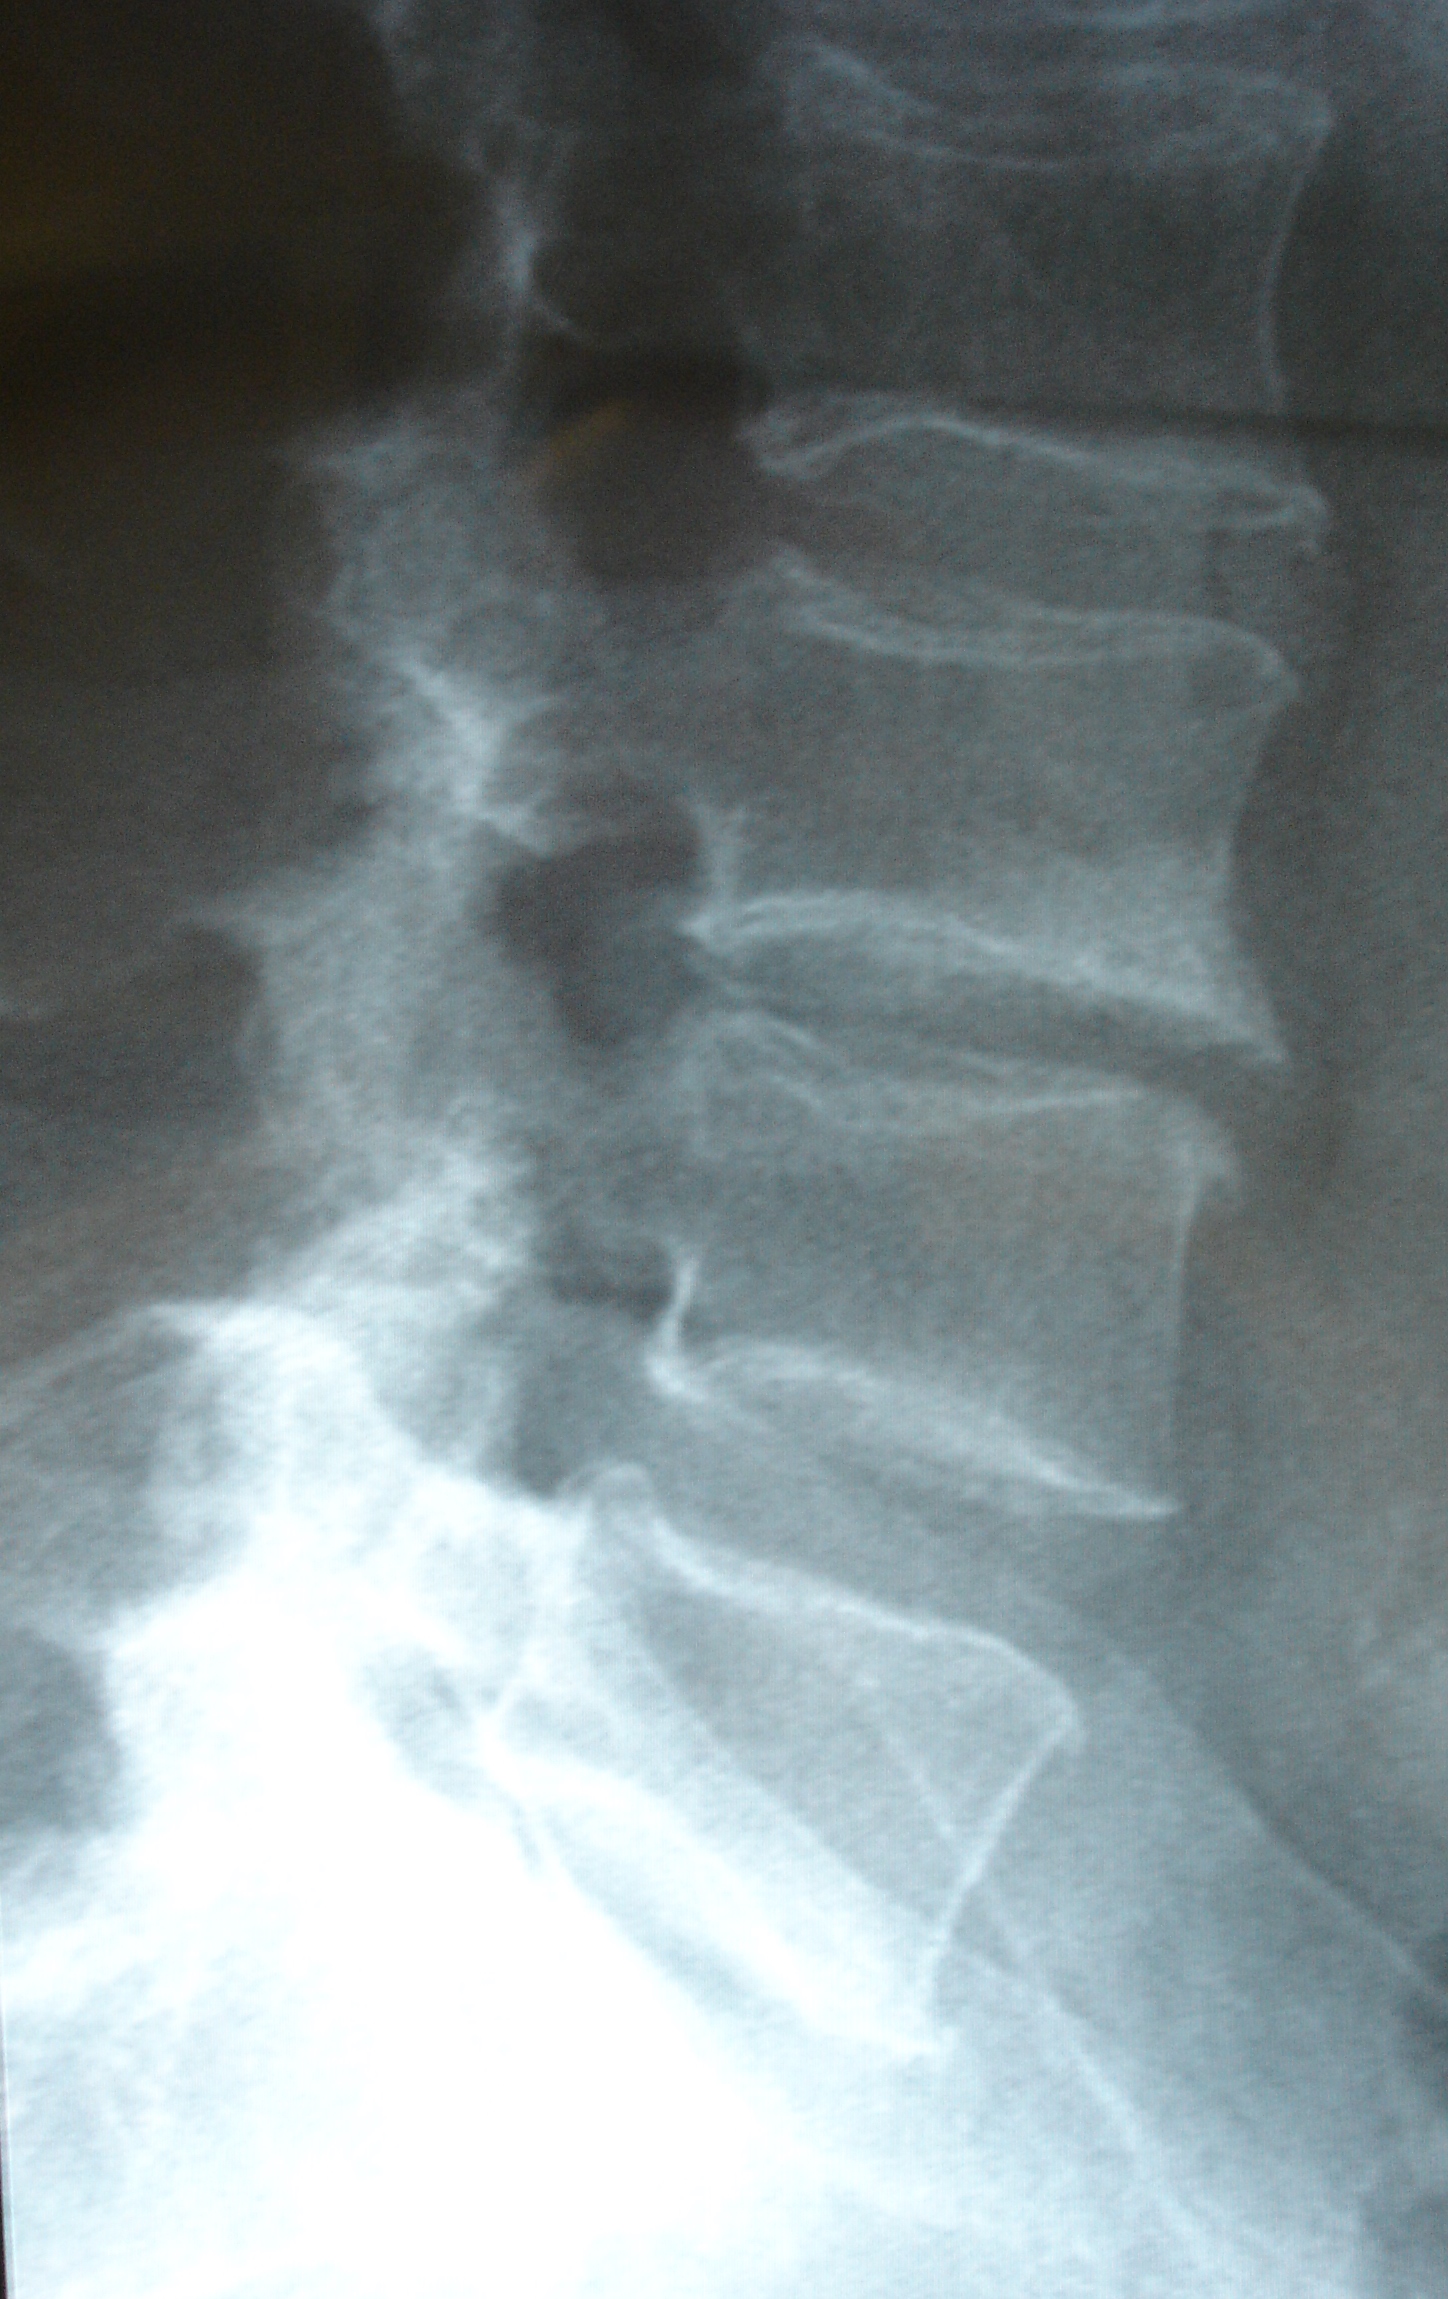

Las imágenes a continuación pertenecen a un caso con una remisión sintomática casi completa y un grado muy alto de satisfacción de la paciente tratada.

En las imágenes de RX y RMN se observan los cambios degenerativos (señalados en rojo las articulaciones interapofisarias artrósicas), también la presencia de múltiples hemangiomas, y las imágenes intraoperatorias de control de los implantes de oro (con flechas).